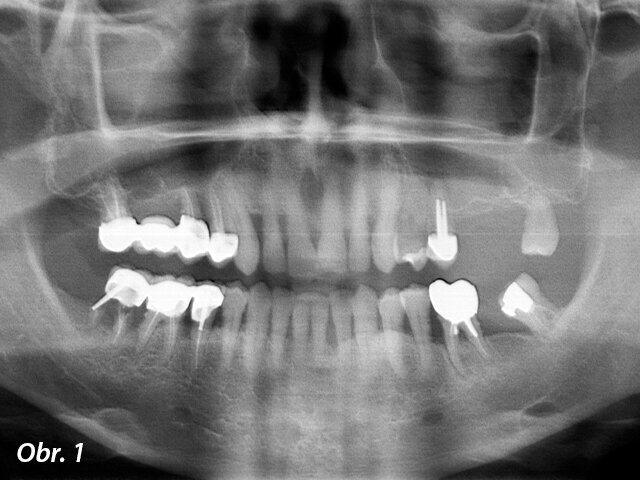

Předoperační RTG: dva premoláry a třetí molár v levé části maxily musely být extrahovány a pod čelistní dutinou nebylo dostatek kosti umožňující zavedení implantátů.

Muž, 56 let se k nám dostavil k rehabilitaci jeho částečně bezzubé levé horní čelisti, stěžoval si na neefektivní žvýkání. Zuby 26 a 27 byly extrahovány a nebyly nahrazeny a zuby 24 a 28 byly viklavé. Zub 25 byl endodonticky ošetřen, ale s periapikálním nálezem. Tyto 3 zuby byly přetíženy se značnou resorpcí kosti a jejich prognóza byla beznadějná. Generalizovaná parodontitis byla stabilizovaná (obr. 1). Jako náhrada zubů 24 a 25 byly zavedeny dva cylindrické samozaváděcí implantáty (Brånemark System Mk IV TiUnite regular platform [RP], Nobel Biocare) v délce 10 a 15 mm a v průměru 4 mm a následně i 35 mm dlouhý zygomatický implantát do pozice 26. Provizorní nefunkční šroubovaná fixní částečná náhrada byla okamžitě spojena se všemi třemi implantáty díky dostatečnému zaváděcímu kroutivému momentu. Pro tuto šroubovanou fixní částečnou náhradu byly použity multi-unit abutmenty (MUA, Nobel Biocare) 3 mm 17°, 2 mm 17° a 3 mm rovný RP. Finální fixní částečná náhrada byla nasazena po 4 měsících hojení (obr. 2–6).